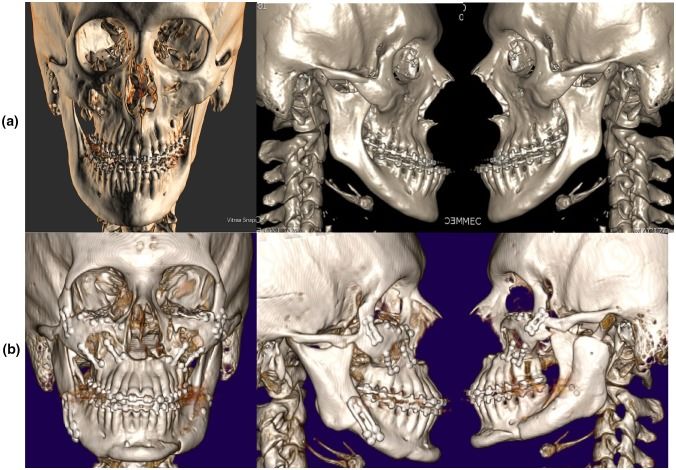

It moves cheekbones upward, give so much under eye support and even change orbital shape. Also widen face and change gonial angle. Is it modified lefort 3?